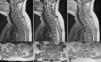

El sarcoma de Ewing es un tumor óseo maligno que en ocasiones presenta afectación extraesquelética, siendo rara la localización epidural. Presentamos el caso de una mujer de 45años que presentó parestesias, debilidad progresiva y retención urinaria. La resonancia magnética mostró una masa epidural desde C6 a D3. Se realizó una laminectomía de C7 a D2 y exéresis parcial de la lesión. El estudio anatomopatológico fue compatible con sarcoma de Ewing. La paciente recibió quimioterapia y radioterapia, no existiendo evidencia de enfermedad a los 8meses de seguimiento. Presentamos una revisión de la literatura de todos los casos publicados de sarcoma de Ewing extraesquelético con afectación epidural.

Ewing sarcoma is a malignant tumour of the bone that sometimes presents extraskeletal involvement, with the epidural location being rare. We report the case of a 45-year-old woman with paresthesia, paresis and urinary retention. Magnetic resonance imaging showed an epidural mass from C6 to D3. Laminectomy from C7 to D2 and partial resection of the lesion was performed. Pathological analysis was consistent with Ewing sarcoma. The patient received chemotherapy and radiotherapy, without evidence of disease at 8 months follow-up. A review of the literature on all published cases of extraskeletal Ewing sarcoma with epidural involvement is presented.